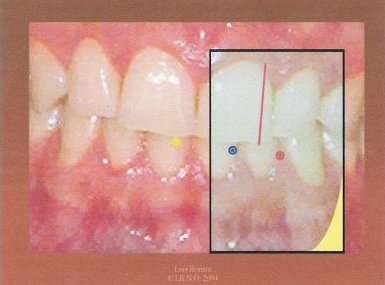

6.-Despegamos el papel en el que queda marcados la línea de referencia y los dos puntos y lo adherimos sobre una plantilla previamente fabricada.

7.- El resultado final nos indica tanto los grados de los ángulos como los milímetros de desplazamiento.